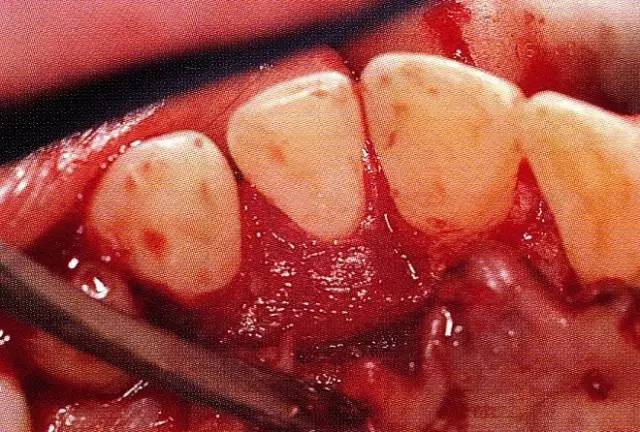

案例3   針對(duì)3壁性垂直性骨缺損使用非吸收性膜進(jìn)行再生治療,再翻瓣時(shí)進(jìn)行骨形態(tài)修整的病例。

▲圖7-1  左下6近中可觀察到3壁性垂直性骨缺損。此病例考慮到齦瓣供血關(guān)系,在前磨牙部位進(jìn)行了減張切開,沒有進(jìn)行縱切開。并利用刮治器、牙周外科用車針進(jìn)行了徹底的骨缺損部位搔刮。